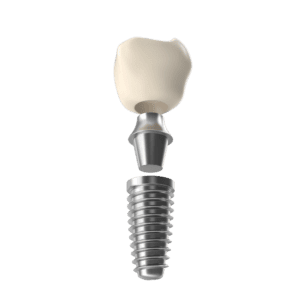

Ist ein Zahn verloren gegangen, so kann er häufig durch ein Zahnimplantat ersetzt werde. Ein Implantat ist eine kleine Titanschraube, die in den Kiefer eingesetzt wird und dort fest verwächst.

Ist ein Zahn verloren gegangen, so kann er häufig durch ein Zahnimplantat ersetzt werden. Ein Implantat ist eine kleine Titanschraube, die in den Kiefer eingesetzt wird und dort fest verwächst. Anschließend können Kronen,

Brücken oder ein herausnehmbarer Zahnersatz daran befestigt werden. Voraussetzung dafür ist ein ausreichendes Knochenangebot.

Diese Arbeiten werden computerunterstützt und mit der Genauigkeit eines Hundertstelmillimeters durchgeführt. Danach wird der Knochen an der betreffenden Stelle vorsichtig aufgebohrt und das Zahnimplantat eingesetzt. Das

geschieht, dank einer genau dosierten, örtlichen Betäubung, absolut schmerzfrei für den Patienten. Nach einer Heilungsphase von drei bis fünf Monaten, die ein Provisorium überbrückt, wird die endgültige Krone auf der neuen

Zahnwurzel befestigt und der Patient bekommt ein Tragegefühl, wie er es von seinen natürlichen Zähnen her kennt. Insofern sind Zahnimplantate die optimale Wiederherstellung des natürlichen Zustandes, unabhängig ob als

Wird das Zahnimplantat zusammen mit einer vollkeramischen Krone gemeinsam eingesetzt, ist das Ergebnis an Funktionalität, Festigkeit, Dauerhaftigkeit und Ästhetik nicht mehr zu übertreffen. Die Farbgebung der Krone wird den

umliegenden Zähnen angepasst, kein Metall kann das Zahnfleisch am Übergang zur Krone irritieren und der neue, künstliche Zahn wird seinem Träger wieder zu einem gewinnenden Lächeln verhelfen.

Implantate ersetzen die fehlenden Zähne einschließlich der Wurzel, sie werden an ihre ursprüngliche Stelle in den Kieferknochen eingesetzt. Diese sichere Alternative zum ursprünglichen Zahn ist in der modernen Zahnheilkunde anerkannt und

hat sich seit über 30 Jahren bewährt. Die Erfahrungen beruhen weltweit auf fundierten Erkenntnissen. Implantate bestehen aus Titan und werden daher – ohne allergische Reaktionen hervorzurufen – problemlos vom Körper angenommen. Durch die

natürliche Belastung der Knochenzellen wird durch das Implantat der natürliche Knochenabbau und somit auch der Zahnfleischschwund verhindert.